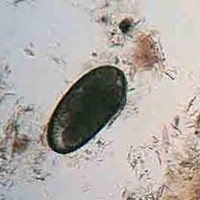

świerzbowiec uszny

jajo-badanie mikroskopijne